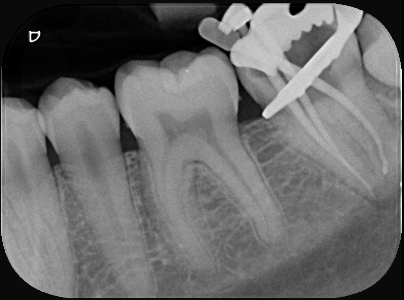

Dr Cosmo explains one patient he had last week where the patient delayed treatment for a hole on a back tooth. The patient was aware of the hole, but due to life’s other commitments, he delayed his visit to the dentist. Here are the photos of his hole – note the mushy appearance of decay which has infected his nerve. It has then spread through the tooth and cause the infection to spread to his lower jaw. This caused a swelling that hurt to touch. In his case, we commenced root canal therapy in an attempt to relieve his pain and keep his tooth. See https://sydneysmilecare.com.au/endodontic-root-canal/ for more information.

Of course we want to prevent these kind of pain to you, but it’s important every six months you come for check-up and cleans to ensure we catch any problems early. In the photo below – this is a rubber dam that we use to protect you from our instruments and irrigants. After we have cleaned out the inside of the tooth, we place medication inside to kill off any remaining infection. Sometimes it requires multiple appointments to clean and resolve the infection. We take x-rays of the tooth assess the extent of decay, the complexity of the tooth and the proximity of local structures that may be at risk of treatment.